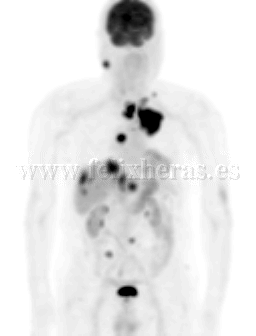

Cáncer de pulmón